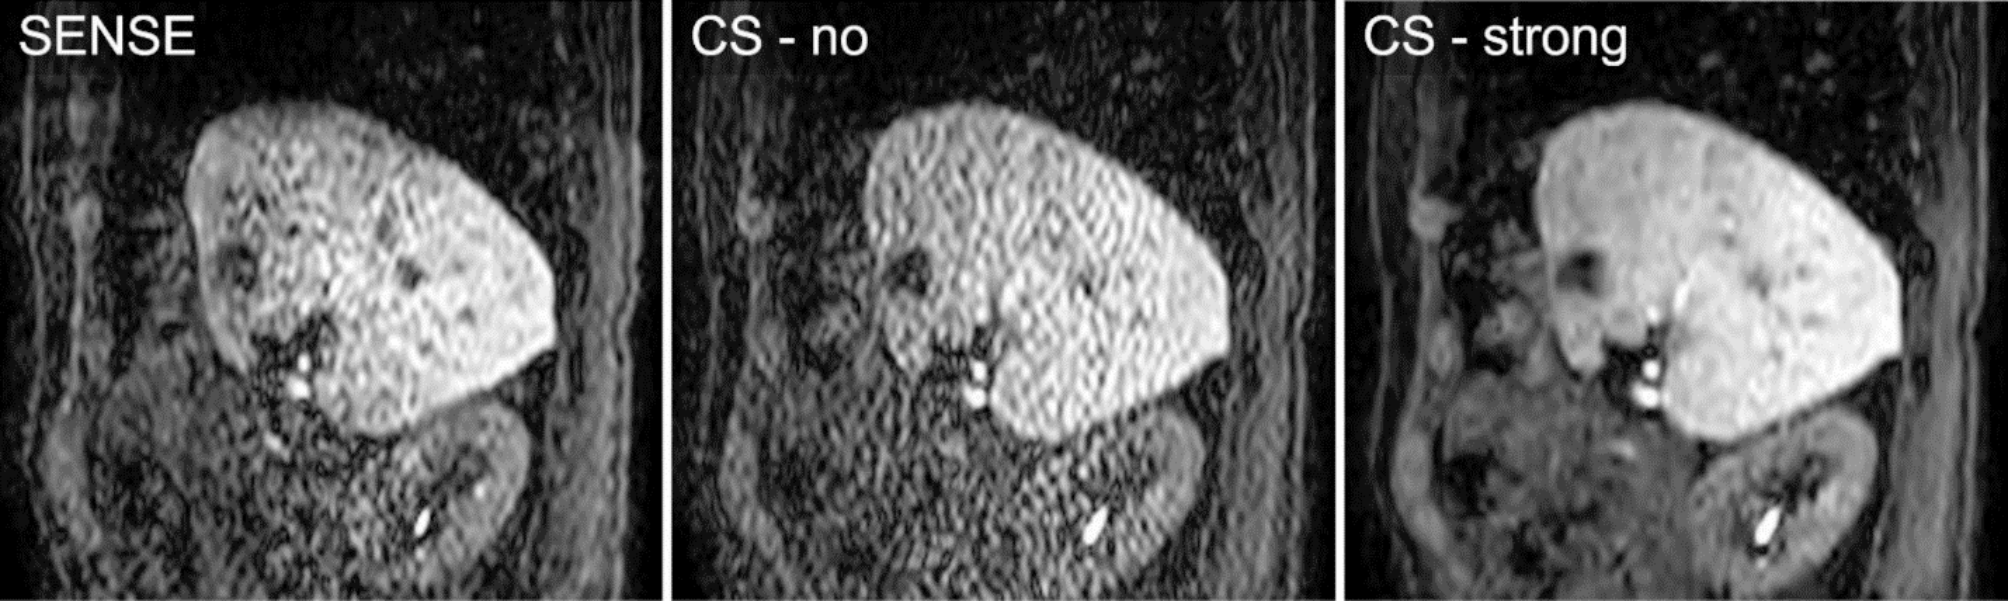

Fig. 8

Representative cine-magnetic resonance imaging images with SENSE, CS-no, and CS-strong. Image artifact caused by parallel imaging is evident in the center of the image with SENSE. Mild image artifact is distributed through the whole range of the image with CS-no, whereas the artifact is reduced in the image with CS-strong. SENSE, sensitivity encoding; CS, compressed SENSE.